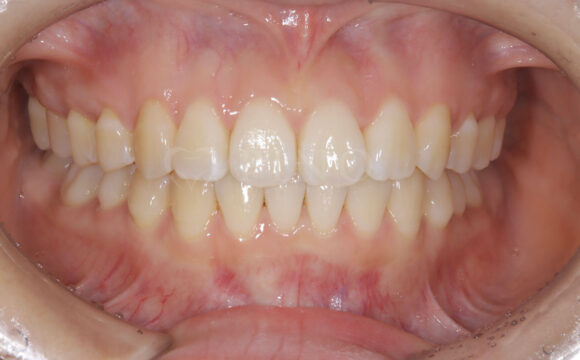

症例4:噛み合わせが深く、下の歯が見えないのが気になる(10代女性)

主訴 噛み合わせが深い、下の歯が見えない 診断名 過蓋咬合(かがいこうごう) 治療方法 マウスピース全顎矯正 抜歯 なし オルソパルス なし 治療期間 1年1ヶ月 費用 746,000円 副作用・注意点 矯正後の後戻りを防ぐためリテーナーの使用が必要となる -